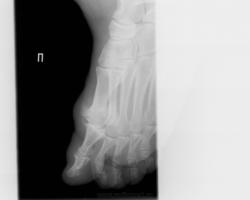

Похоже подагрический артрит, есть характерные тофусы

И я похожую на эту картинку подтвержденную подагру видела.